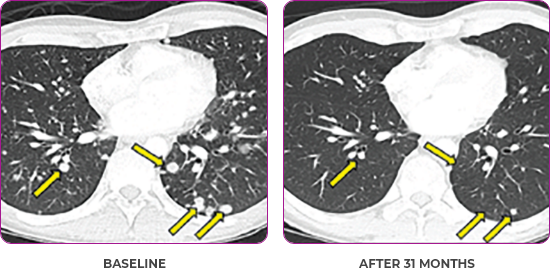

PATIENT CASE:

METASTATIC, RAIa-REFRACTORY,

PAPILLARY THYROID CANCER1,2

- 33-year-old male

- Progression on RAI and first line systemic therapy

- PRa after 2 cycles of VITRAKVI® (larotrectinib)

- Confirmed partial response on VITRAKVI lasting 55 cycles

VITRAKVI treatment1

- VITRAKVI 100 mg twice daily orally

Response to VITRAKVI1,2

- Confirmed partial response (92.6% reduction in target lesions)

- Treatment continued for 55 cycles

- VITRAKVI was well tolerated; patient did not have to discontinue due to AEa

- No treatment interruptions or dose reductions

aAE, adverse event; PR, partial response; RAI, radioactive iodine.

Response in primary and metastatic lesions1

Images courtesy of Dr Steven Waguespack.

aPR, partial response; RAI, radioactive iodine.